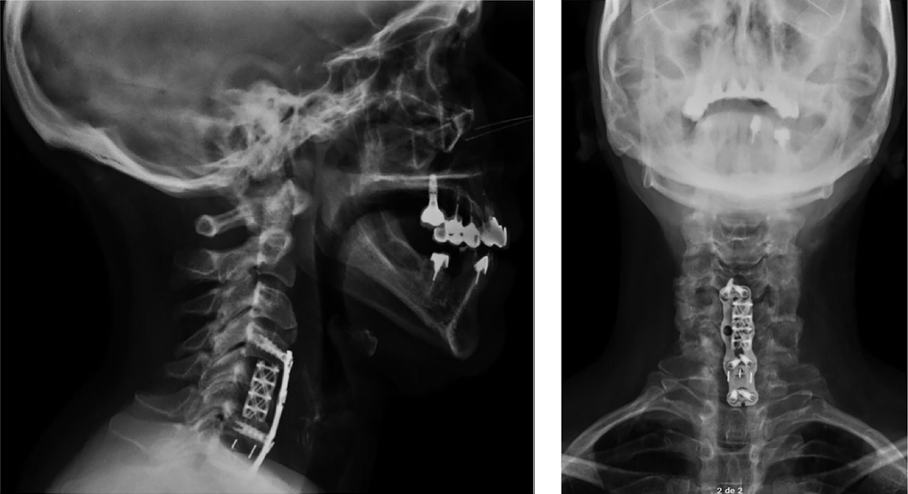

Discectomía y retirada LVCP C6-7, corpectomía subtotal C5 retirando LVCP y duramadre al aire. Reconstrucción con Piramesh y hueso local. Caja cornestone C6-7 con hueso y placa Zevo con tornillos C4-6 y C7.

Ausencia de dolor cervical y parestesias. Hoffmann negativo.